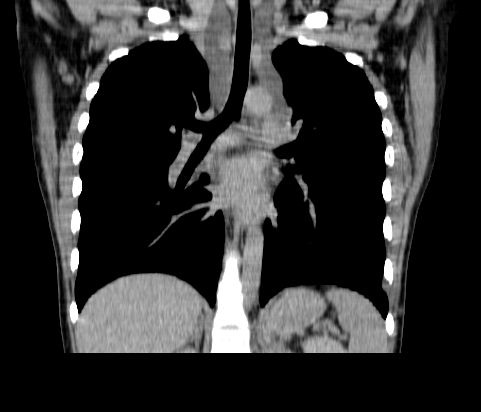

胸部